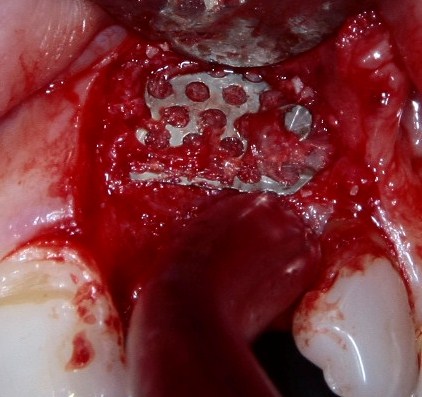

Что же касается нерезорбируемых мембран… Было дело, работал с Gore-Tex (дорого, очень дорого), титановыми сетками (заколебался потом доставать) и тефлоновыми Cytoplast:

результат:

или

с трудом выковыриваем сетку и ищем имплантат:

чтобы поставить формирователь: